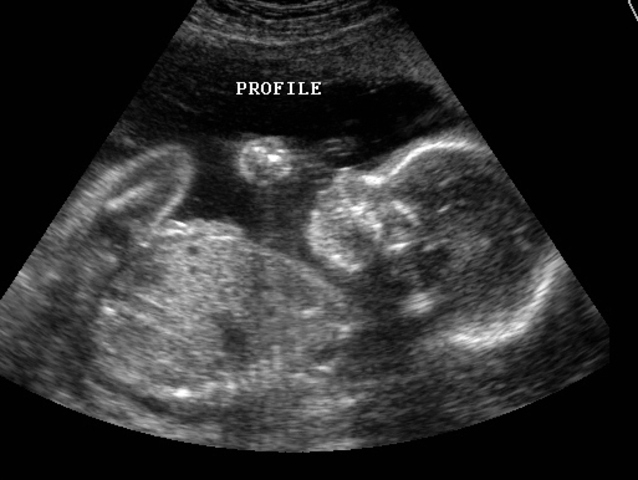

2d ultrasound3